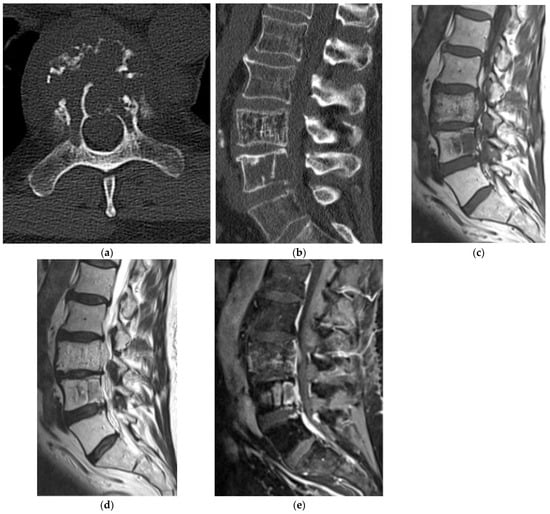

2.5.2. Aneurysmal Bone Cyst